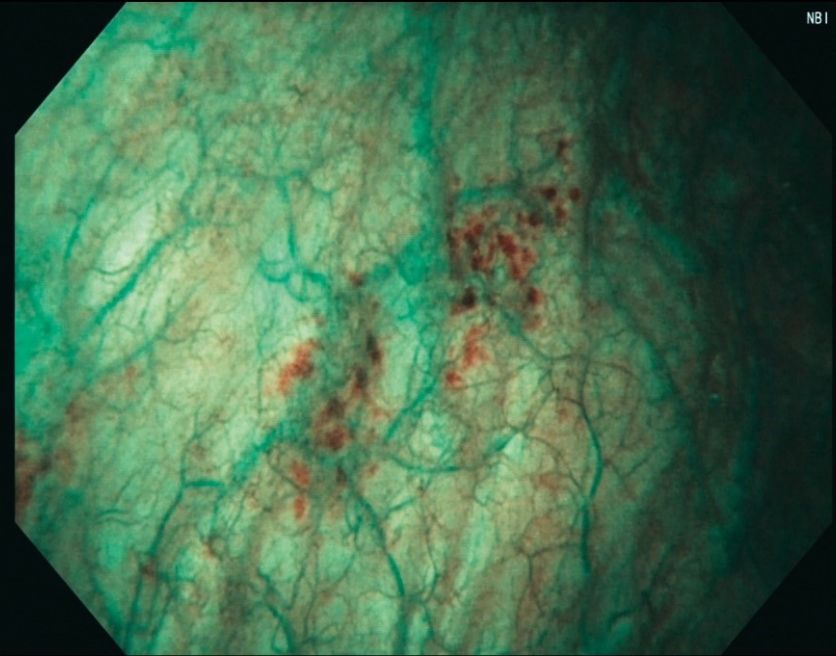

Compatível com a tecnologia NBI:

NBI™ é uma tecnologia de imagem avançada que aumenta a visibilidade dos vasos e outros tecidos na superfície da mucosa.

O NBI™ funciona filtrando a luz branca, devido à característica de absorção de luz pela hemoglobina e pela rede de vascularização da mucosa. Esta tecnologia proporciona um contraste visual da superfície e estruturas capilares.

Estudos demonstram que NBI ajuda a visualizar: